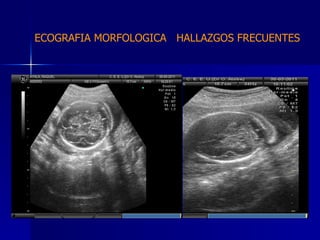

DTFRC-2007 ECOGRAFIA MORFOLOGICA  HALLAZGOS FRECUENTES   GENITOURINARIA DISPLASIA RENAL MULTIQUISTICA  3 HIDRONEFROSIS  2 QUISTE DE OVARIO FETAL  1 SISTEMA DIGESTIVO DILATACION INTESTINAL  2  SISTEMA ESQUELETICO   PIE BOT  2  20 % 6 % 6 %

DTFRC-2007 ECOGRAFIA MORFOLOGICA  HALLAZGOS FRECUENTES   OTROS HIGROMA QUISTICO  2 ENFERMEDAD ADENOMATOSA PULMONAR  1 ARTERIA UMBILICAL UNICA  2 HIDROPS FETAL NO INMUNE  1 QUISTE DE CORDON UMBILICAL  1 ALTERACION DE LIQUIDO ANMIOTICO  2 SINDROME TRAFUSIONAL FETO FETAL 1 LABIO LEPORINO  2 TOTAL  12  42 %